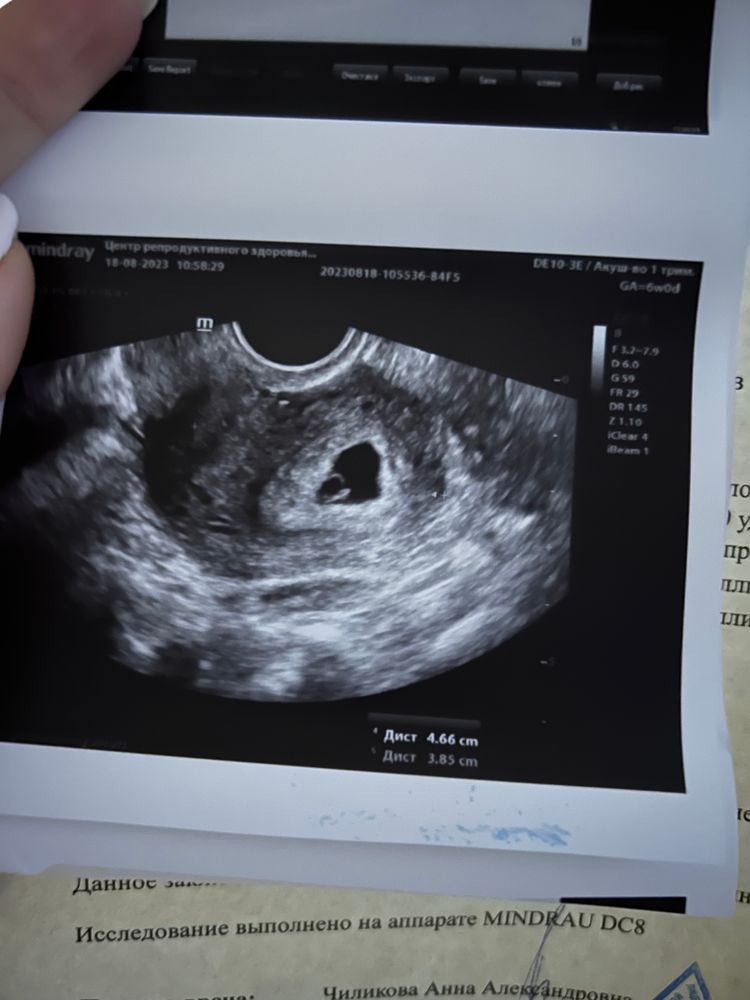

23 дпп узи